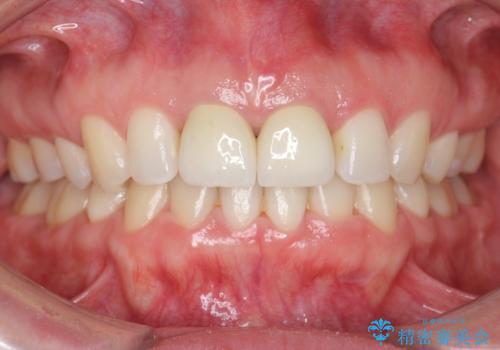

その後、マージンが舌側が深い状態だったため、歯ぐきの手術(歯周外科処置:APF)を行ってから最終的なセラミックを装着しました。

- 費用(概算)

- 117万円(矯正治療:90万円 上顎両側 1 ジルコニアクラウン(スペシャル):13万円x2、仮歯:1万円x2 矯正用高強度仮歯:2万円x2 歯周外科手術(APF):5万円)費用は治療当時の料金となります

終了時

治療について

患者様には快くご協力いただき、しっかり口元を下げることができました。